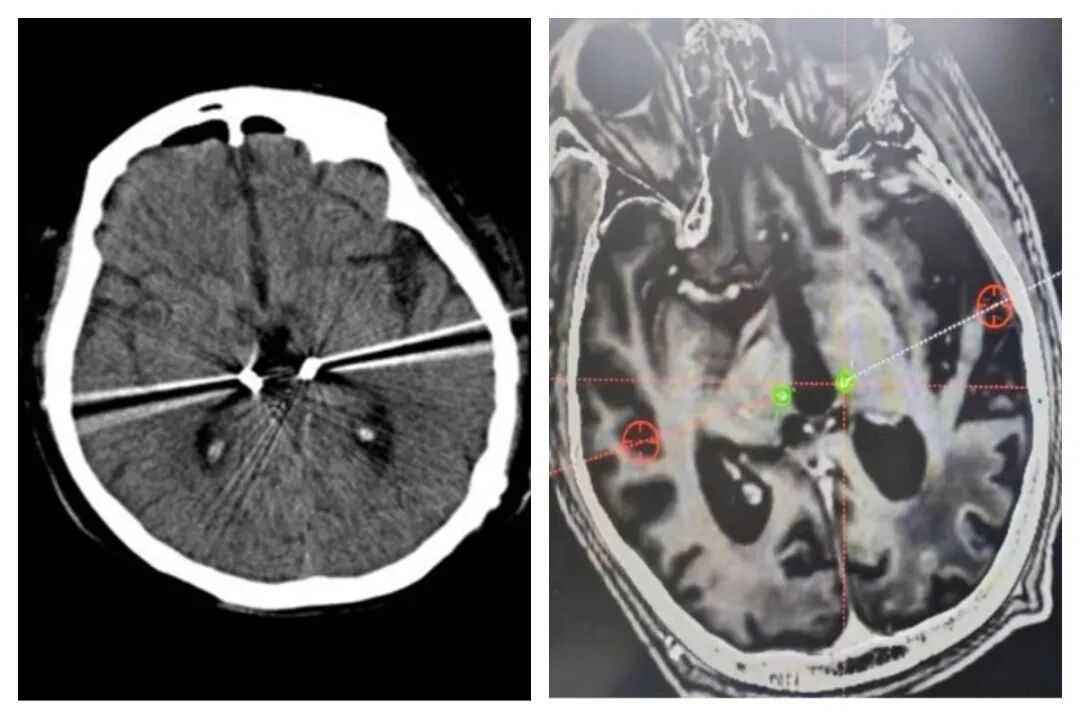

“DBS”(Deep Brain Stimulation)是一种借助CT、MRI来定位的立体定向手术。这项治疗的精髓在于其对精确度的极致追求:首先,患者需佩戴Leksell立体定向头架,以确保在手术过程中的精确定位。随后,将患者颅脑的高分辨率MR图像数据导入到专业的计算机系统中,以实现对手术靶点核团的精确定位。

在手术过程中,电极被精准地植入到预定的核团中,这一步骤的精确度对于治疗效果至关重要。接着,这些电极将与一个精巧地植入在胸壁皮下的刺激器相连。这个刺激器能够产生规律的电脉冲,直接作用于目标核团,以调节其神经活动,从而达到治疗的目的。